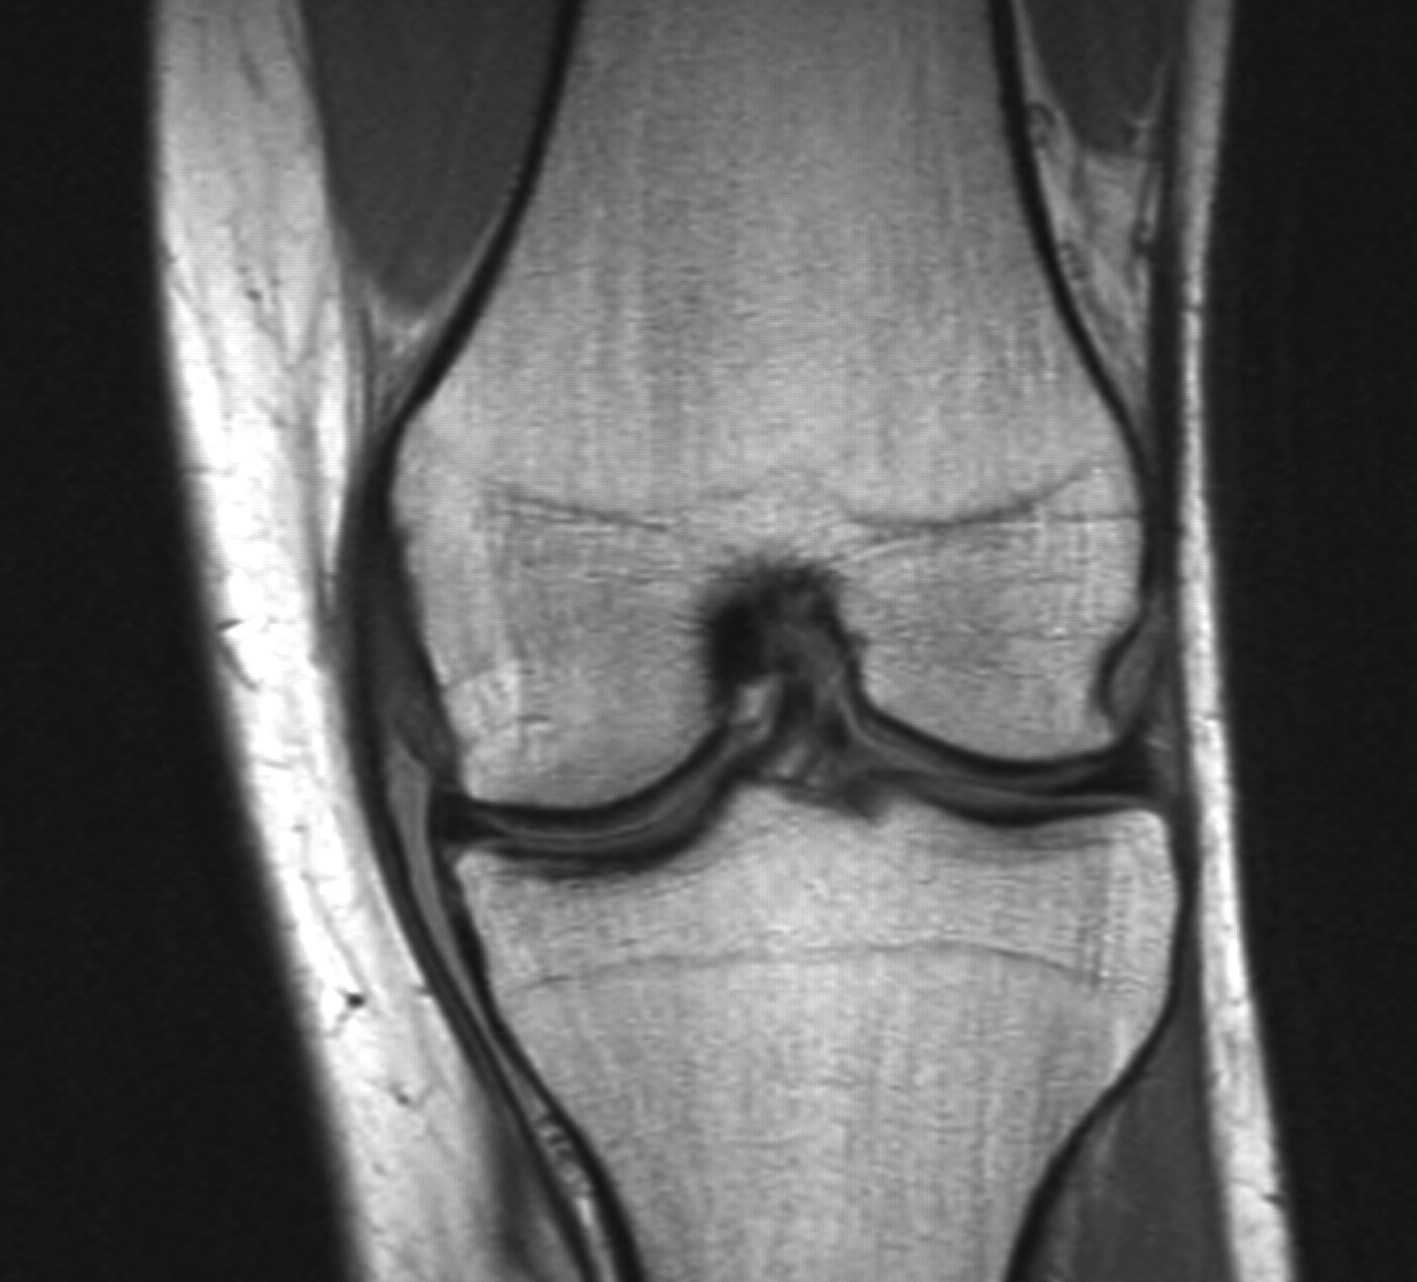

Purpose: To identify patient characteristics indicative of a medial collateral ligament injury.